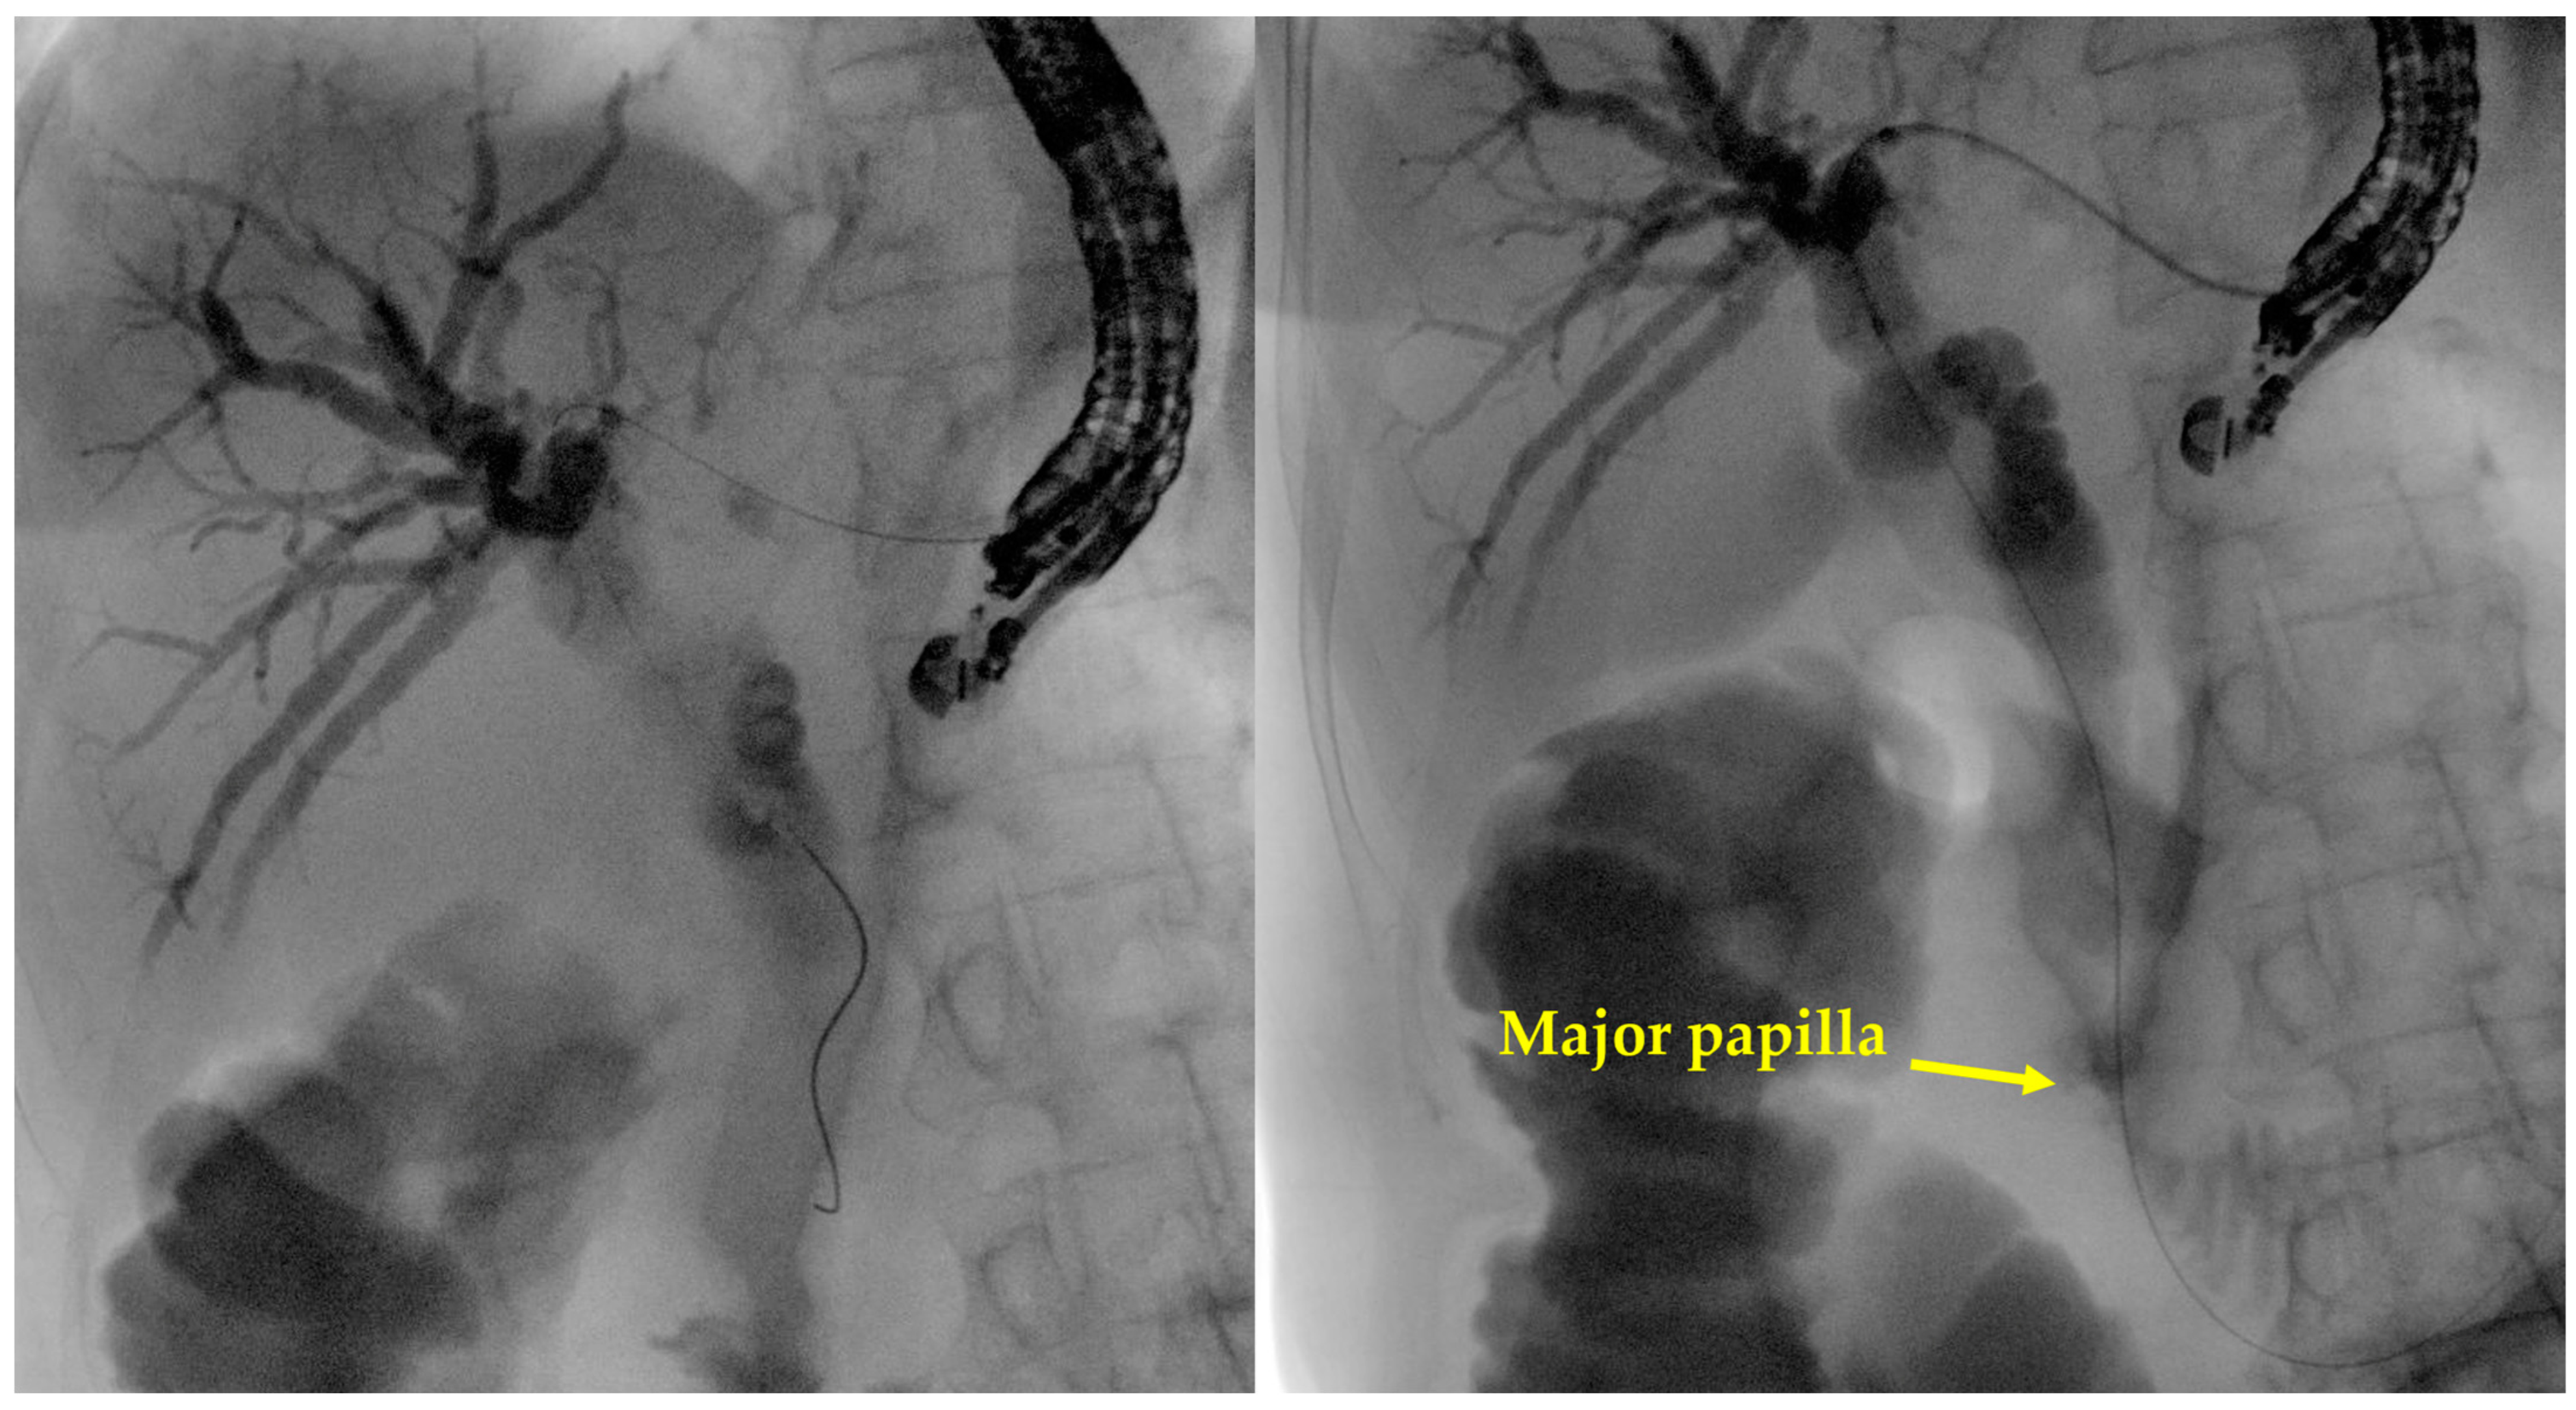

- Intrahepatic bile duct puncture

- Fluoroscopy and guidewire manipulation into the biliary tree